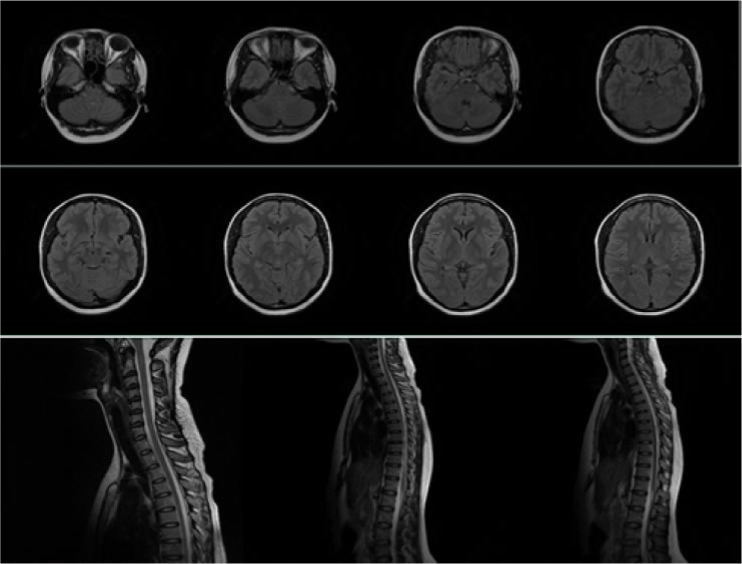

Objective: The aim of this article is to report a classical case of NMOSD with AQP-4 IgG seropositivity and normal brain, cervical and thoracic MRI findings.

Result: We report a 25-year-old Nigerian woman who presented with recurrent and alternating weakness, pain and numbness of all limbs, associated with episodic painful left-sided tonic spasms and urinary incontinence. She had earlier had symptoms of recurrent, episodic and alternating loss of vision in both eyes, associated with ocular pain.Examination findings revealed an intact mental status, no cranial nerve deficit and no focal limb weakness. Right-sided deep tendon reflexes were exaggerated. Vital signs were within normal limits. Brain MRI, Cervical spine MRI and Thoracic spine MRI all revealed normal findings. Serum aquaporin-4 IgG assay returned positive with a titer of 1:32.She was commenced on high dose steroids and there was gradual improvement of symptoms.